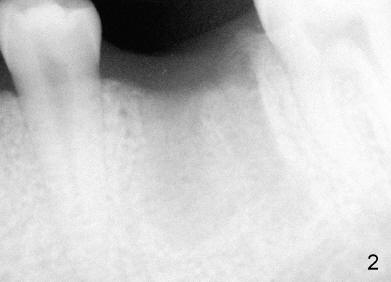

A 22-year-old man requested extraction of the tooth #19 (Fig.1).  X-ray was taken 3 and 8 months post extraction, respectively (Fig.2,3).  A 6x17 mm Tatum tapered implant was placed (Fig.4,5). A 5 mm (in diameter) 0 degree unipost (5 mm in height) was prepared 7 months after implant placement. Due to limited space, time was spent for extraoral and intraoral reduction of the abutment.